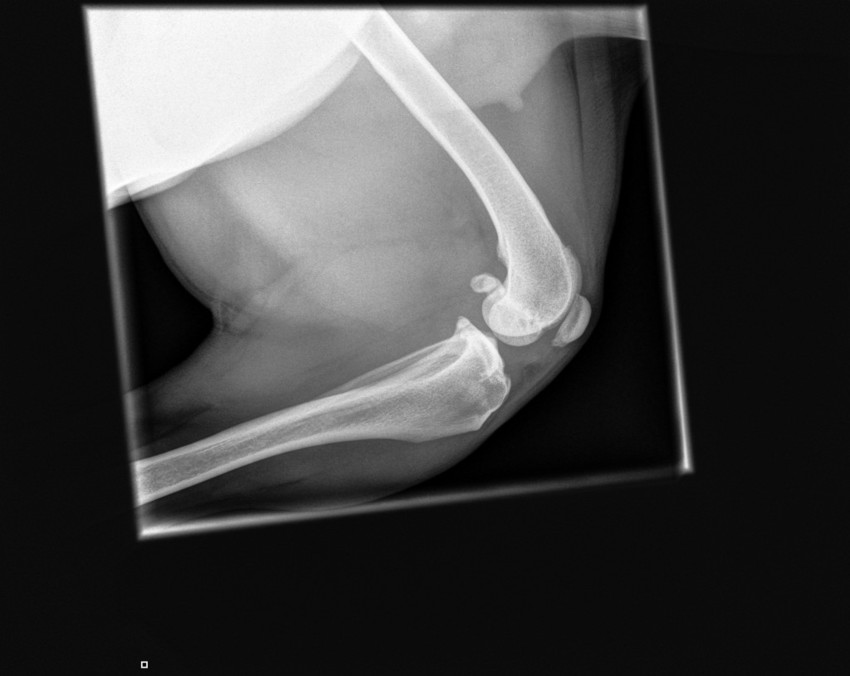

Voor de degene die t interesant vinden of er verstand van hebben vinden hier de fotos van haar knie

Â

Yara heeft dit in haar elleboog (lpc) en loopt ook niet mank.

Wel zijn (mede) hierdoor haar gewrichten niet mooi gegroeid en is een bijkomend probleem dus artrose in de elleboog.

En daar komt haar stramheid vandaan, want dat is hetgene waar ze last van heeft. Maar niet het stukje bot zelf.Â

Er waren een paar kleime stipjes te zien wat wss duid op artrose. Maar voor de zekerhijd even doorgestuurd naar de specalistÂ

Ze verwacht tot nu toe artrose in haar knieÂ

Maar asistente zegt dat ze naar de utreg moet de kliniek daar voor beter onderzoek en dat die denkt aan de voorste kruisband en dat ze een nieuwe moetÂ

We moeten naar den orthopeed toe die gaat voelen hoe ver t is en operatie nodig is en hoe verder want dan kunnen ze niet ziem op de fotoÂ